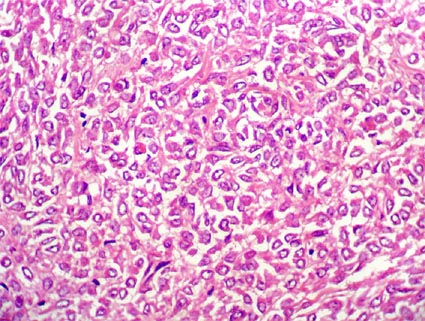

Hallazgos microscópicos: hay un aspecto variable, con áreas parecidas o similares al carcinoma convencional, pero suelen tener un aspecto más variable y muchas veces se ven con células más grandes, voluminosas, irregulares, como si viesemos un carcinoma convencional "raro", con carcaterísticas singulares. En muchos hay células claras, aspecto papilar o en nidos; podemos ver microcalcificaciones. En otros casos las células grandes y voluminosas tienen citoplasma granular eosinofílico. Los núcleos son redondos y usualmente grado 2 y 3. El número de mitosis es variable, en nuestros casos pocas (entre 1 y 3 por 10 campos de gran aumento). Hay poca anaplasia. Se dice que los tumores con fusión ASPL-TFE3 tienen un aspecto más papilar y los que tienen la fusión PRCC-TFE3 un patrón más compacto.

Figura 16. Carcinoma renal en una mujer de 17 años; masa que reemplaza gran parte del órgano y se extiende al retroperitoneo. En este caso el aspecto recuerda el de carcinomas con células granulares. El estudio de inmunohistoquímica (realizado en otro centro) fue positivo para TFE3. (H&E, X400).uerda